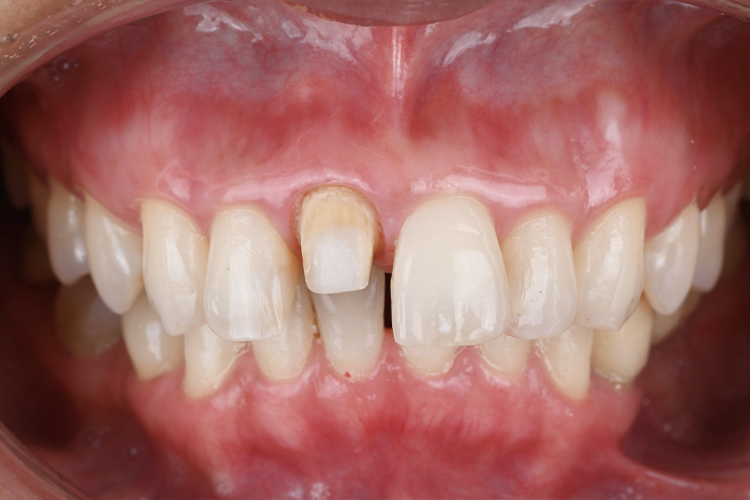

仮歯セット

技工士が作成した仮歯をもとに、チェアサイドにて数回調整を重ね、患者様の気に入った形態・理想の形態を一緒に模索します。

ラボプロビ(仮歯)は『本番前のリハーサル』です。

補綴物装着後に「もっとこうしたかった…」「こんなはずじゃなかった…」では遅く、ラボプロビ(仮歯)の段階で最終形態のイメージをしっかり擦り合わせることで、双方が満足のいく補綴物を装着することができます。

仮歯が最終的な補綴物の形態になるので、妥協してはならない治療の過程といえます。